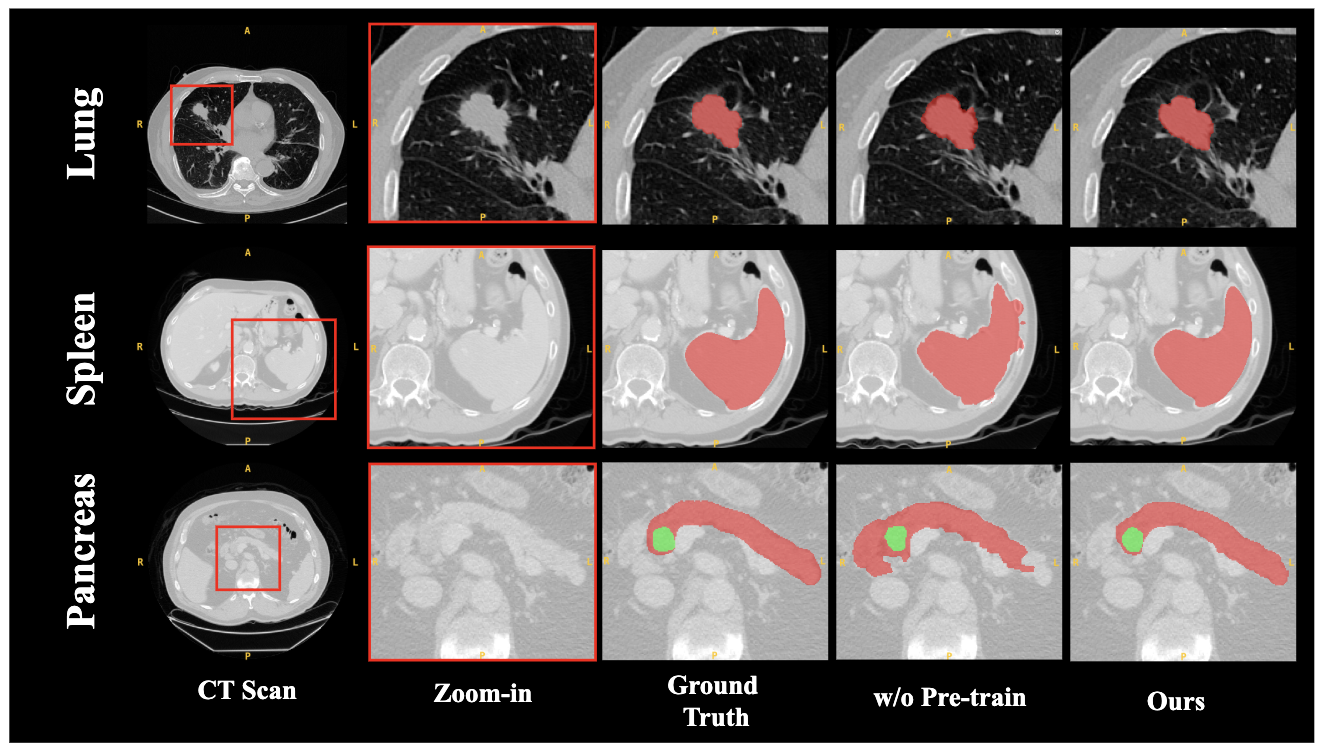

To rigorously evaluate the contribution of each core component in our proposed SAM2-3dMed framework, we conduct systematic ablation experiments. All studies are performed on three datasets under identical training settings and hyperparameters. We design three experimental configurations: 1) w/o Pre-train: Training SAM2-3dMed from scratch, without leveraging the pre-trained SAM2 Image Encoder and Memory Attention modules; 2) w/o SRPP: Removing the Slice Relative Position Prediction module; 3) w/o BD: Removing the Boundary Detection module.

As summarized in Table 2, the ablated models exhibit significant performance degradation compared to the full SAM2-3dMed, confirming the necessity of each component.

Impact of Transfer Learning: The w/o Pre-train configuration performs the worst across all metrics and tasks. Compared to our full model, its removal leads to an average Dice score drop of 0.1708 and an average NSD drop of 0.2142 across the three datasets. Specifically, the Dice score decreases by 0.1624 on Lung, 0.0814 on Spleen, and a significant 0.2686 on Pancreas. This underscores the critical role of transfer learning in leveraging pre-trained representations for 3D medical segmentation, especially when annotated data is limited.

To validate the effectiveness of leveraging pre-trained weights for initializing our model, we conducted a comparative experiment. We compared our full model, which utilizes weights pre-trained on a large-scale natural image dataset from original SAM2, against an identical model trained from scratch (“w/o Pre-train”). The results of this comparison and visualization are detailed in Table 3 and Fig. 4.

The empirical results clearly demonstrate that pre-training brings substantial performance improvements across all three datasets and all evaluation metrics. For instance, on the challenging Pancreas dataset, employing pre-training boosts the Dice score from 0.4353 to 0.7039 (a 61.7% relative improvement) and reduces the 95th percentile Hausdorff Distance (HD95) dramatically from 47.9971 to 14.9232. Similar significant gains are observed on the Lung dataset, where the Dice score increases from 0.6003 to 0.7627, and on the Spleen dataset, which sees a rise from 0.8913 to 0.9727.

This consistent and significant performance enhancement underscores the crucial role of transfer learning in our approach. The features learned from large-scale datasets provide a superior initialization for the network’s weights, enabling the model to converge to a much better solution and achieve higher segmentation accuracy, especially in medical imaging scenarios where annotated data is often scarce.

Refer to caption

Figure 4: Visual comparison of segmentation results with and without Pre-training.